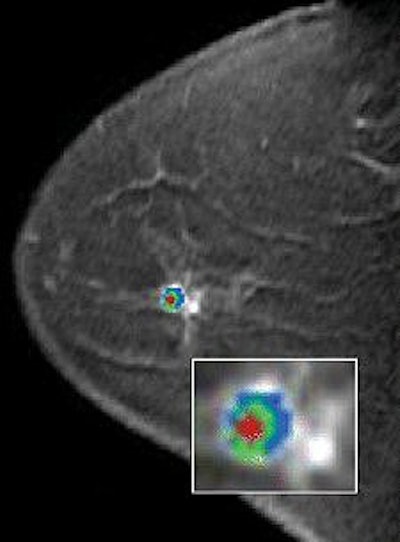

| A 49-year-old woman with mammographically occult contralateral breast cancer detected on MRI. Above, initial contrast-enhanced sagittal MR image. Below, CAD overlay shows lesion as having significant enhancement and mixed pattern of washout, plateau, and persistent delayed enhancement. If pixel value on delayed series decreases by more than 10% of its immediate contrast-enhanced value, that pixel is color-coded red on monitor, indicating washout of contrast material. If pixel value increases by more than 10%, it is color-coded blue on monitor, indicating persistent enhancement. If pixel value does not change in either direction by more than 10%, it is color-coded green for plateau enhancement. |

According to the results, 24 lesions were identified by pathology as benign and nine were malignant. "All malignant lesions showed significant enhancement using the program at all thresholds, producing a sensitivity of 100%," the authors wrote.

"False-positive rates for the computer-aided assessment compared with the original radiologist assessment were reduced by 25% at a 50% threshold, 33% at an 80% threshold, and 50% at a 100% threshold for enhancement," they added.

In terms of kinetic enhancement pattern types in eight benign and eight malignant lesions, all showed a wide range of washout, persistent, and plateau. There was a significant overlap of benign and malignant lesions.